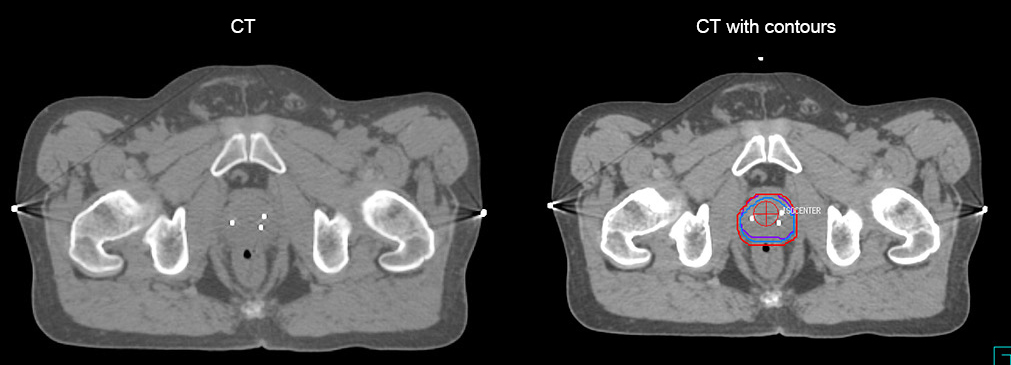

Impressive clinical benefits for prostate

“The biggest problem for CT-based planning, especially in prostate, is you can’t see the cancer very well,” says Dr. Stevens. “On CT it can be quite challenging to see the edge of the prostate especially at the apex. When the edge of the prostate can’t be delineated well on CT, radiation oncologists will increase their margins a little bit so they don’t miss it, but that can also increase toxicity.”

“Using MR, the prostate is well delineated. We quickly see the edges of cancerous tumors like in prostate cancer, and as normal structures can be defined, we can optimize the treatment plan to protect these organs and their normal function. This can potentially improve the outcome. And it improves workflow as well. We can contour more quickly, confident that the tumor is going to be in the field.”

“When a patient registers, first CT simulation and MR simulation are done, followed by CT-MR registration on Pinnacle3. Then the target and normal organ delineation is performed on MR images. Meanwhile we create a reference CT image for online treatment and localization correction. During the treatment phase we can perform additional MRI scans to visualize the anatomy changes and create an adaptive plan. This plan basically adapts the treatment plan to the changes.”